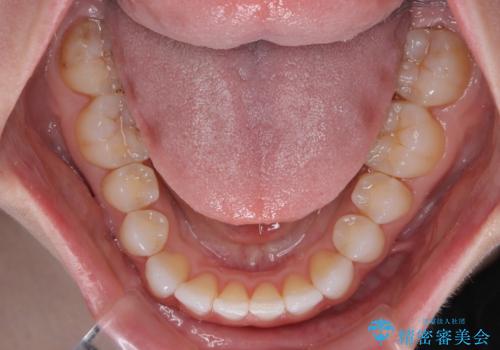

前歯のデコボコをインビザラインで綺麗に

- 上下前歯の叢生を気にして来院された患者様です。

インビザラインでの治療を希望されていて、デコボコの程度が中等度であり、安価なパッケージにて対応可能と判断されたため、インビザライン・モデレートを用いて矯正治療を行うこととしました。

インビザライン・モデレートは、製作できるアライナーの枚数に制限があるため、移動可能な量に限りがあるものの、インビザライン・ライトよりも枚数が多いため、幅広い症例に対応可能です。